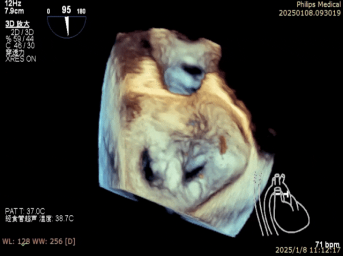

术中二尖瓣夹系统进入瓣下并捕获瓣叶